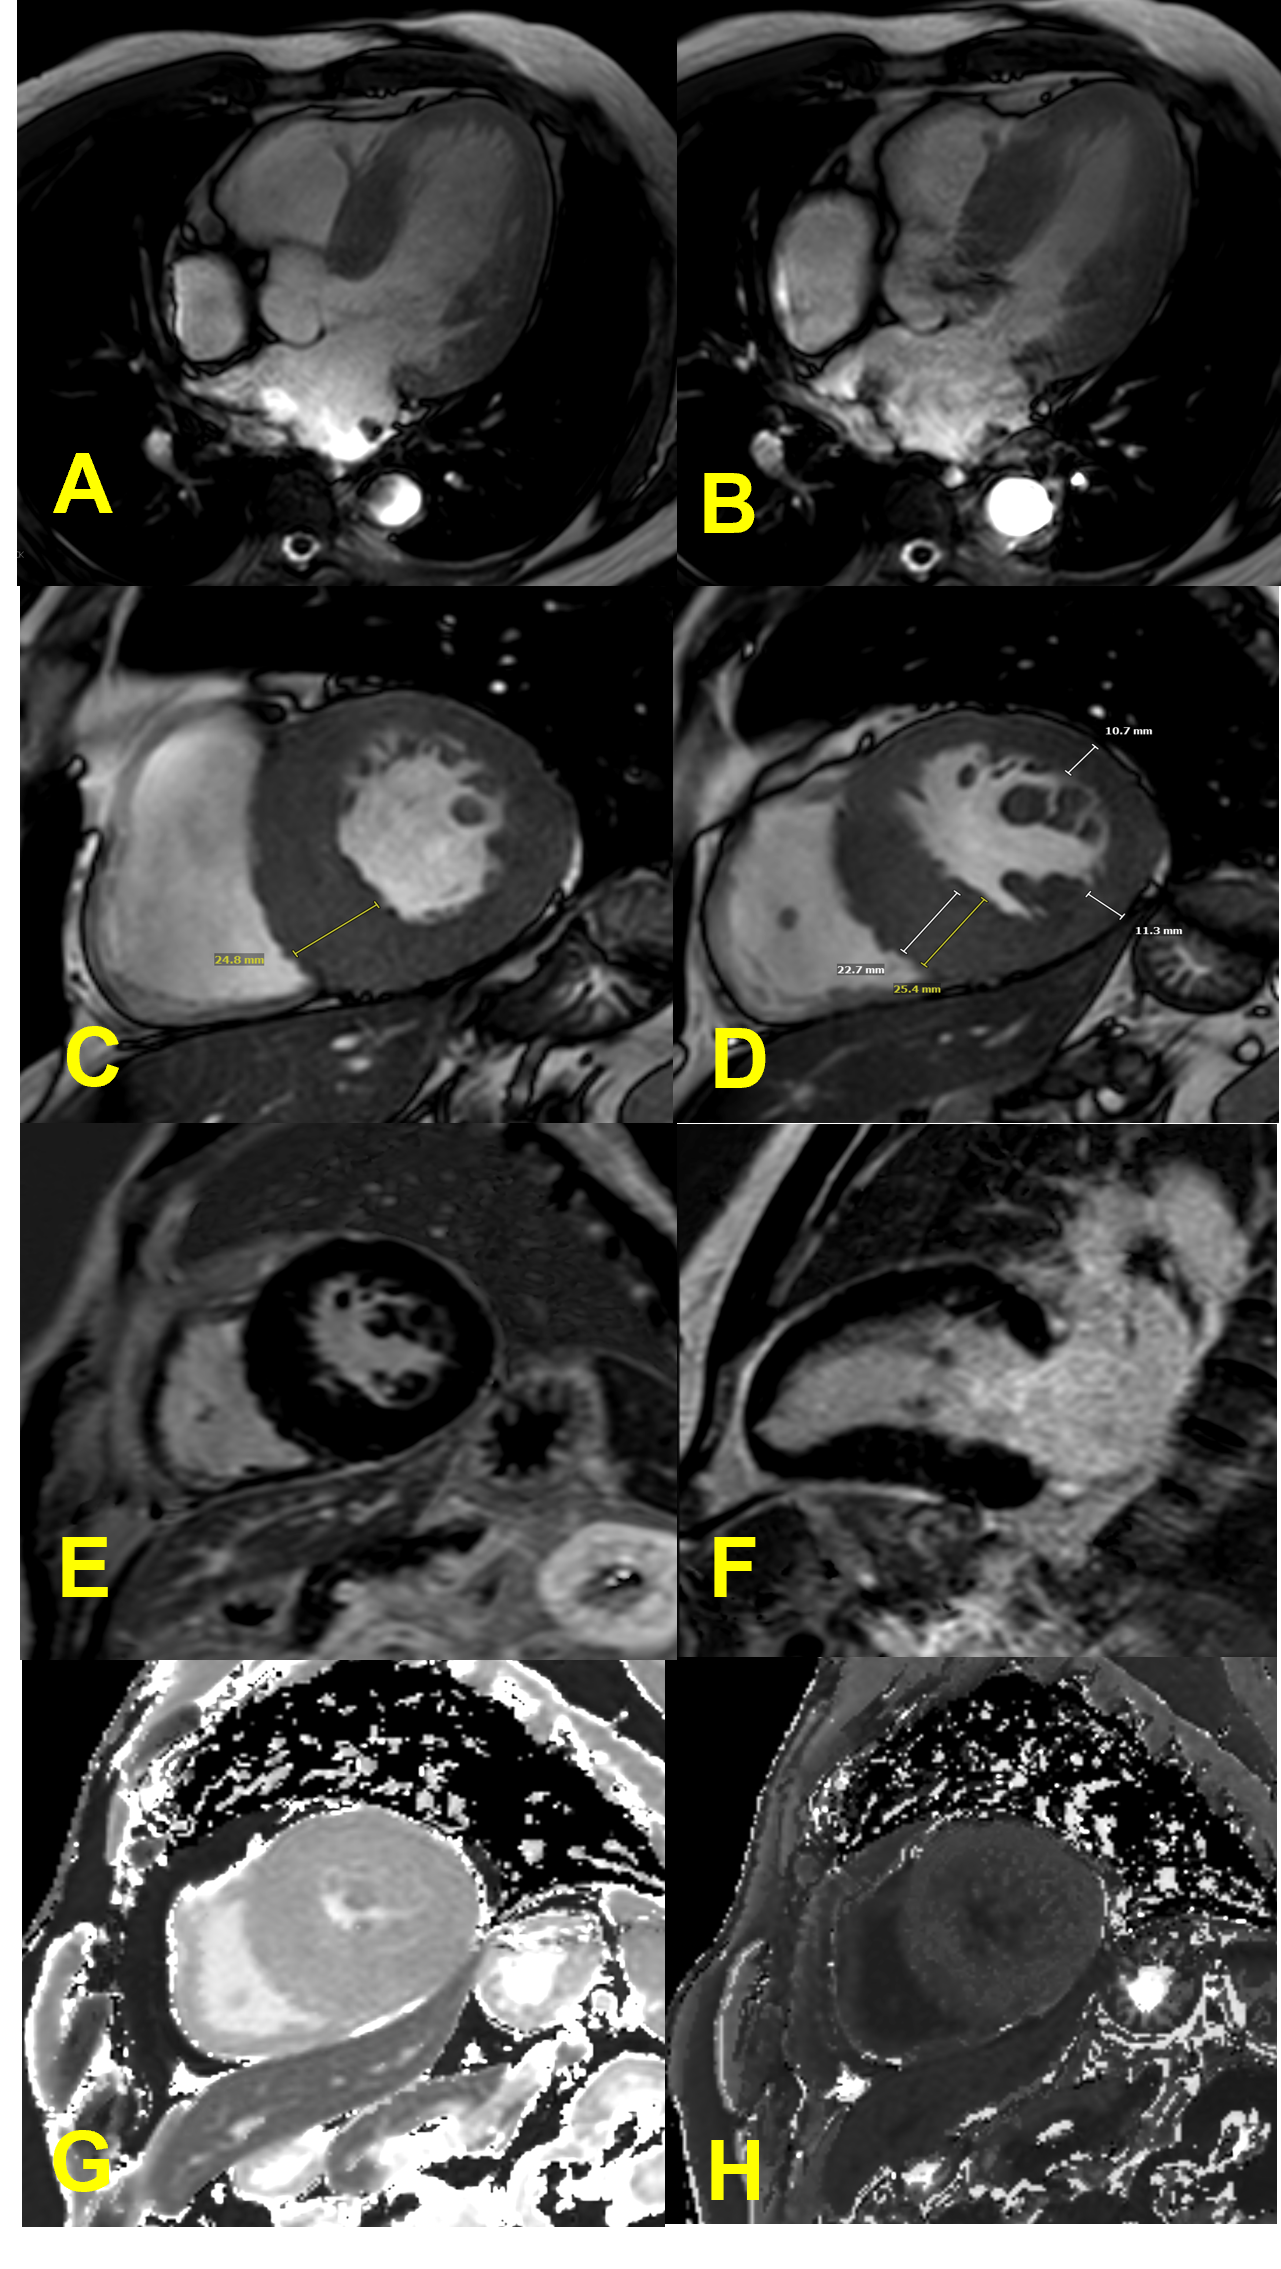

.png)